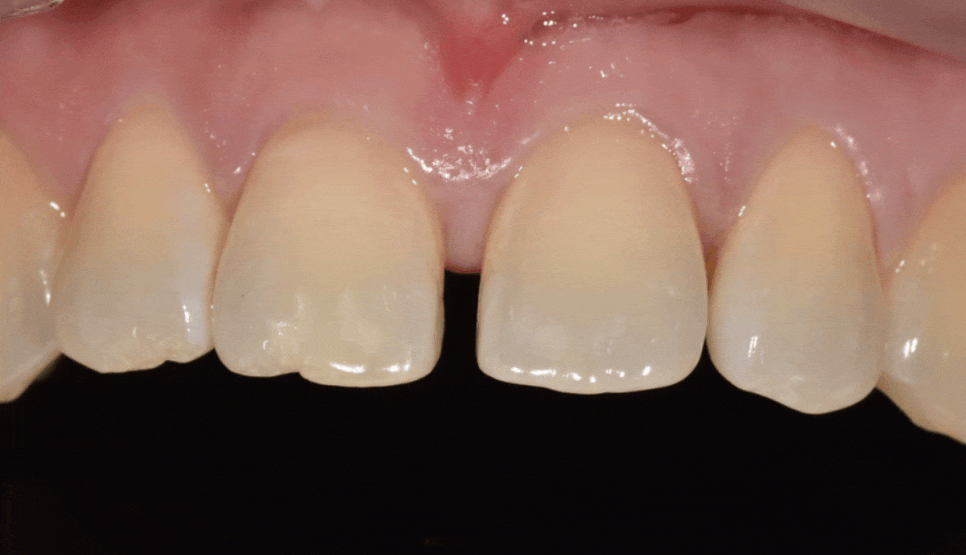

얼마 전 저희 치과를 찾으신 환자분은

가운데 앞니가 벌어진 상태였고,

동시에 왼쪽 위 어금니(#26)도

상실된 상태였어요.

치료 결과

고덕동 치간 이개, 위 앞니 벌어짐

라미네이트를 통해

앞니 4개의 균형을 맞추고 나니,

단 며칠 만에 인상이 훨씬 단정해지셨습니다.